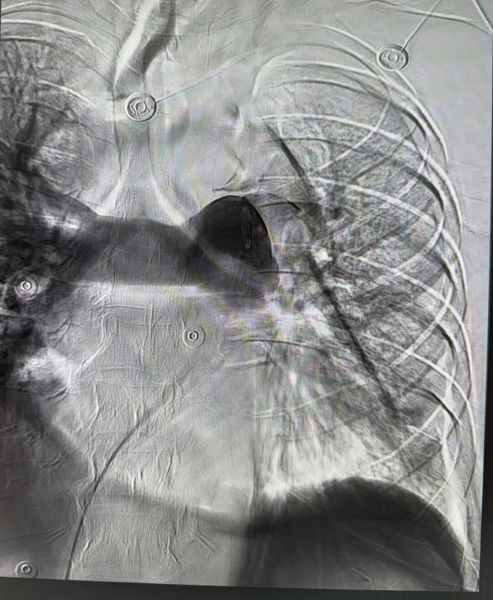

在手术室无影灯下,普外甲乳血管外科王胜主任与林雨丰医生为患者进行了肺动脉造影。造影结果令人倒吸一口凉气:患者的左肺动脉主干已经完全闭塞,大量血栓将血管腔完全堵死,这正是导致患者呼吸困难急剧加重的“罪魁祸首”。

情况刻不容缓,专家团队立即按照预案实施抢救。通过导管精准定位,直接将溶栓药物注入血栓部位进行肺动脉溶栓治疗。随着药物起效,堵塞的血管逐渐再通。为防止下肢静脉血栓再次脱落堵塞肺动脉,专家们又为患者成功在下腔静脉植入了滤器,为患者的生命安全加上了一道“保险阀”,手术顺利完成。术后,专家团队考虑患者肾功能问题,给予了积极的水化等保护肾功能的治疗。复查结果显示,原本肾脏异常情况并未加重。